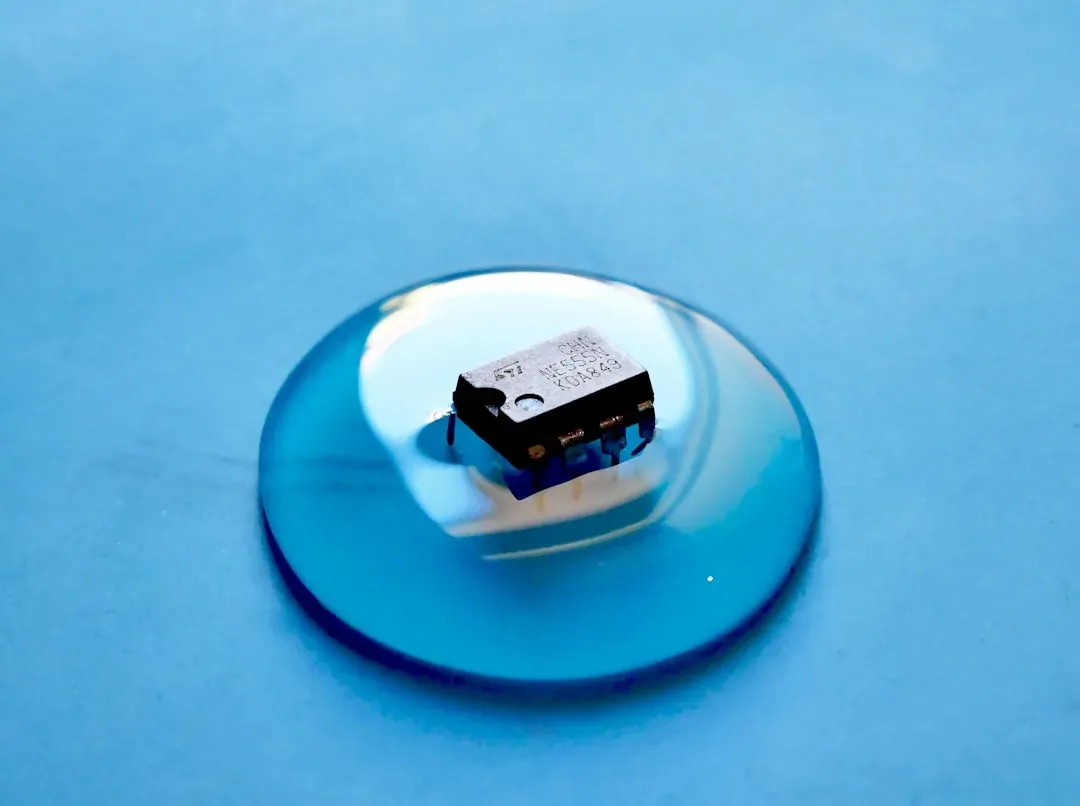

Quantum Computing and Drug Discovery: Compressing Years into Days

Simulating molecules accurately is brutally hard with classical computers, especially when electrons interact in complex ways inside large drug candidates or protein targets. Quantum computers, in theory, are built to handle exactly that kind of problem, because they work with quantum bits that obey the same rules as the particles they’re trying to model. Over the last few years, there’s been rapid progress in early quantum algorithms that can approximate molecular energies or reaction pathways in ways classical machines struggle to match, especially as systems scale up.

Pharmaceutical companies and research groups are already experimenting with hybrid approaches that pair quantum chips with classical supercomputers. The goal is not sci‑fi magic, but shaving months or even years off the early drug discovery pipeline by narrowing down promising candidates more intelligently. Instead of blindly screening huge libraries, scientists can use quantum-inspired models to predict which molecules are most likely to bind to a target, resist mutations, or avoid toxic interactions. The technology is still limited by noisy hardware and small system sizes, but even partial gains in accuracy or speed could have a massive impact on how quickly new treatments reach the clinic.